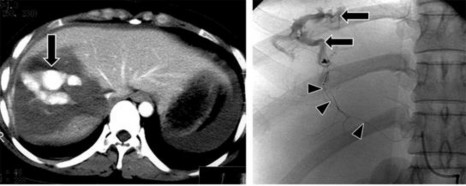

Hình 1.8: Rách gan và đụng dập – tụ máu nhu mô (mũi tên ngắn) vùng không có phúc mạc phủ gây tụ máu sau phúc mạc (mũi tên dài).

Nguồn: Shanmuganathan K, Mirvis SE [21].

Hình 1.11: Tổn thương mạch máu (mũi tên).